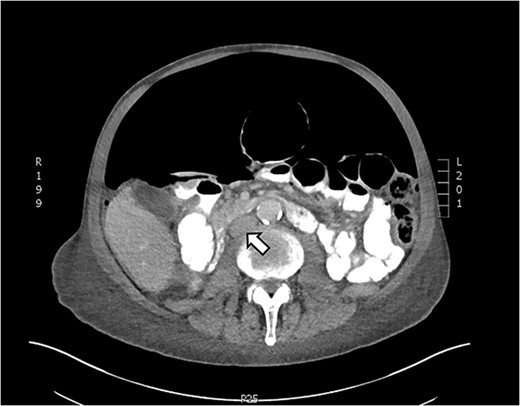

Axial CT showing tension pneumoperitoneum and collapsed inferior vena cava (arrow)

On presentation, his temperature was 37.8°C, and he was hypotensive at 100/45 mmHg and tachypneic with a respiratory rate of 22. He was in moderate respiratory distress and was placed on 2 L oxygen via nasal prongs. On abdominal examination, mild distension was noted with lower abdominal tenderness with rebound tenderness and guarding in the right lower quadrant. He had normal leukocytes of 5 × 109 /L (N: 4.0–11 × 109/L) and lactate was normal at 1.6 mmol/L (N: 0.5–2.2 mmol/L). X-ray chest showed free air under the diaphragm suggestive of pneumoperitoneum (Fig. 1). A CT abdomen was performed showing large-volume free air suggestive of a viscous perforation and moderate volume of free fluid in the abdomen (Fig. 2). The site of perforation was not confidently established on the study. There was generalized oedema of the right side of the colon with multiple loops of dilated small bowel. His Physiological and Operative Severity Score for enumeration of Mortality and Morbidity (POSSUM) score would be 81% predicted mortality and 98.8% predicted morbidity if he were to undergo an emergent laparotomy operation. Family discussion was made, and he decided not to proceed with operative management. He was managed conservatively with piperacillin-tazobactam and decompressed with nasogastric tube insertion. As the days progressed, his abdomen became increasingly distended and tympanic, but not peritonitic. We repeated a CT chest and abdomen three days after initial admission and it was reported he had tension pneumoperitoneum (Fig. 3). CT with oral contrast was also performed to exclude an upper GI perforation.

Here, we present a case of spontaneous idiopathic pneumoperitoneum with CT findings of tension pneumoperitoneum managed successfully with bedside decompression using a pig-tail catheter attached to a chest drain. Failure of decompressing the tension pneumoperitoneum may result in hemodynamic instability and ischemia of abdominal organs as large pneumoperitoneum may compress on the inferior vena cava reducing venous return to the heart. CT findings of tension pneumoperitoneum include marked elevation of diaphragm, decreased thoracic volume and/or compression of the inferior vena cava [10]. Emergency percutaneous needle compression using 16G cannulas have been used in cases for immediate decompression of the tension pneumoperitoneum [11]. Our patient had a high POSSUM score; for him to undergo a laparotomy would place him at a high mortality and morbidity risk. Here we demonstrate successful management of idiopathic tension pneumoperitoneum with pig-tail catheter attached to an intercostal drain.